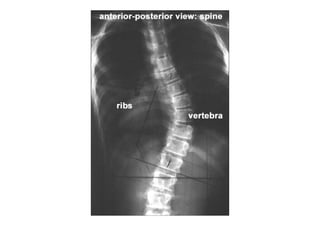

RADIOLOGIA DO

TRAUMA DO ESQUELETO

Referência: http://www.accessexcellence.org/RC/VL/